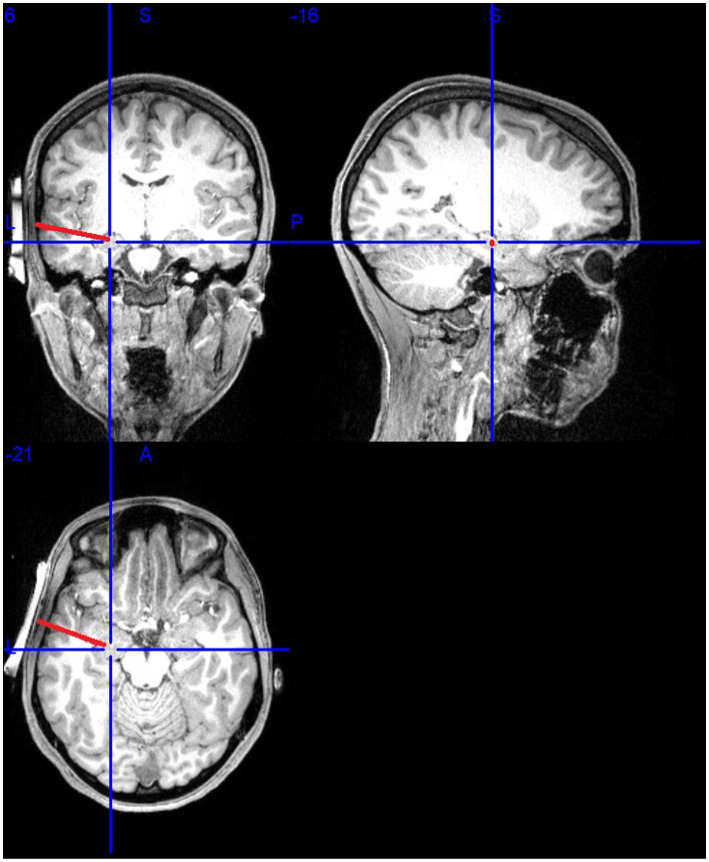

Methods: We aimed to address these gaps in literature in a cohort of 10 healthy individuals. We utilized the well-validated Emotional Face Assessment Task (EFAT), which is designed to robustly engage the amygdala. We selected the fusiform gyrus and the thalamus as our non-target regional comparison measures due to their roles in facial and emotional processing. In succession, participants completed a pre-LIFU baseline fMRI, received 10-min of LIFU neuromodulation, and then repeated the baseline fMRI. To test our hypothesis, we conducted paired-samples t-tests assessing changes in amygdala, fusiform gyrus, and thalamic activation from pre to post scan.

Abstract Image